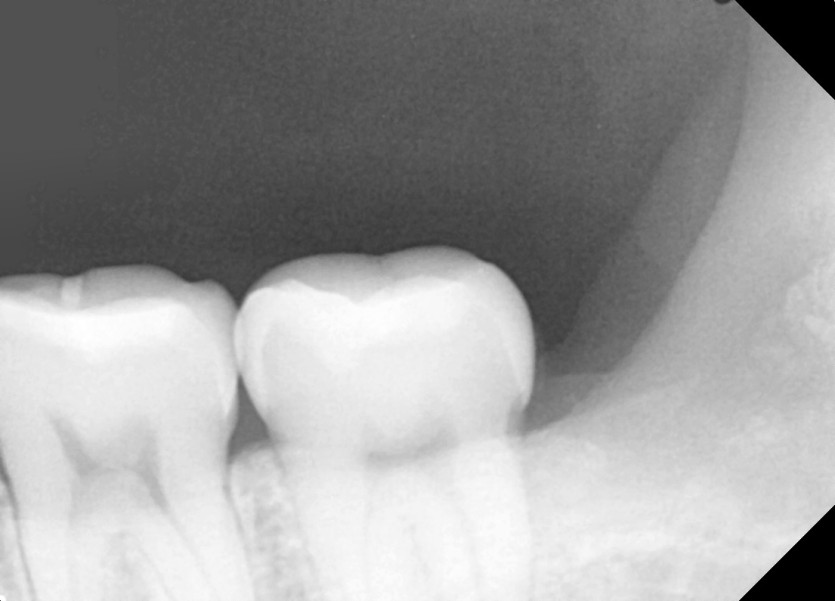

#38 사랑니 발치

구강 외과 전문의가 당일 발치했습니다.